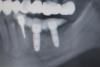

Wasja Опубликовано 4 декабря, 2012 Поделиться Опубликовано 4 декабря, 2012 Есть еще ультразвуковой аппарат Осстел. Правда у него один минус-диагностические штифты стоят денег. Но на тотальных работах применение оправдано. Самое обидное, когда имплантат проворачивается на этапе фиксации большой протезной работы.В этом случае перестановкой имплантата не отделаешься.... Ссылка на комментарий